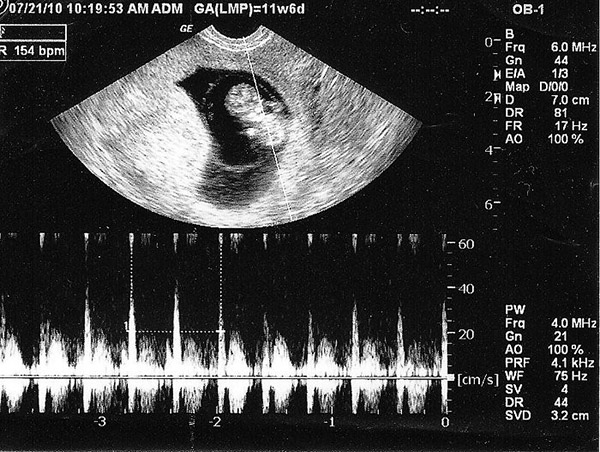

Thai nhi 6 tuần đã xuất hiện tim thai?

Nhiều bé đã xuất hiện tim thai vào tuần 6, nhiều bé đến khoảng tuần thứ 7-12 là rõ rệt nhất.

Tuỳ vào tốc độ phát triển của thai nhi mà nhiều bé vào tuần thứ 6 đã có tim thai, nhiều cháu chưa. Tim thai đã được dần hoàn thiện từ tuần thứ 4 nhưng đến tuần 6, nhịp tim của bé đã đập khoảng 120 – 160 lần/ phút. Tốc độ này gấp đôi người lớn bình thường.

Bên cạnh đấy, nhiều thai nhi sẽ có tim thai ở tuần thứ 7 và tới tuần 12 là quá rõ ràng rồi. Nguyên nhân có thể do tính tuổi sai bị lệch hoặc thời điểm rụng trứng có thể bị muộn so với chu kỳ cuối. Thực chất không làm sao cả, vì cái này cũng có thể do yếu tố di truyền.

Nếu muốn biết chắc thai nhi có tim thai bình thường hay không thì mẹ xem vào khoảng tuần 8 là tốt nhất.